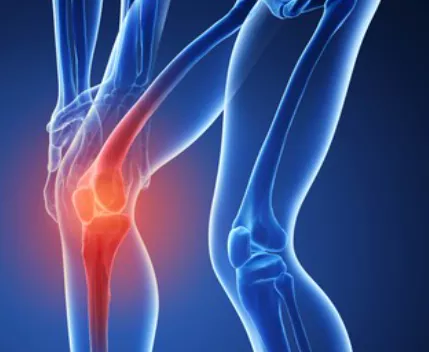

무릎 관절염은 많은 사람들에게 영향을 미치는 흔한 관절 문제 중 하나입니다. 이러한 질환이 있는 환자들은 적절한 운동을 통해 무릎 관절을 더욱 강화하고 통증을 완화하는데 도움을 줄 수 있습니다. 이 글에서는 무릎 관절염에 좋은 운동 10가지 및 주의사항에 대해서 자세히 살펴보겠습니다.

무릎 관절염은 일상생활에 불편을 초래할 수 있지만 적절한 운동과 주의 사항을 준수하면 증상을 개선하고 생활의 질을 향상할 수 있습니다.

위에서 소개한 무릎 관절에 좋은 운동은 무릎 관절을 강화하고 통증을 완화하는데 도움을 주는 것뿐만 아니라, 제대로 수행하면 다른 건강 이점도 얻을 수 있습니다.